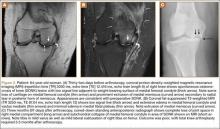

Table 1 lists the demographics and imaging characteristics of the 11 patients—6 had SONK before arthroscopy and 6 developed it after arthroscopy. Comparison of the 11 patients with SONK and the 11 controls is summarized with P values in Table 2. Representative cases that either presented before surgery or developed after surgery are shown in Figures 1 to 4. There were 6 prearthroscopy lesions and 6 postarthroscopy lesions—all 12 in the medial femoral condyle. Eleven of the 12 knees had a medial meniscal tear, and 1 knee had both medial and lateral meniscal tears. In 8 of the 12 knees, the lateral meniscus was normal; in 2 knees, it had mild degeneration; and, in 1 knee, it had a complex tear. Assessment of hyaline cartilage revealed medial cartilage loss ranging from 2A to 3B (median, 2B) in the patients with SONK, and lateral cartilage loss ranging from 0 to 2A (median, 0). At surgery, all knees had a partial medial meniscectomy, and 6 had a partial lateral meniscectomy. Ten of the 12 knees had chondroplasty, 9 patellar and 5 of the medial femoral condyle. Only 4 of the 11 patients with follow-up of more than 1 year went on to joint replacement. Six of the 12 had follow-up of more than 2 years. Of the 6 patients without an identifiable SONK lesion on MRI before arthroscopy, 4 had mild to moderate knee pain 0.5, 2.4, 3.5, and 4 years after surgery. For the other 2 patients, knee replacement was performed 1.5 and 1.8 years after surgery. Of the 6 patients with prearthroscopy SONK, 4 had mild to moderate knee pain 1.5, 3.7, 6.5, and 6.8 years after surgery; the other 2 had knee replacement 0.5 and 1.8 years after surgery. Articular cartilage degeneration and meniscal extrusion were similar (Table 1). In the control group, there was only 1 knee replacement, at 3 years, and the other 11 were functioning 2.6 to 5 years later. The longer follow-up resulted from selection of appropriate controls from the same year. Of the 6 SONK lesions found on preoperative MRI, 3 were read by the interpreting radiologist before surgery as possible SONK lesions, 2 were read as insufficiency fractures, and 1 was read as a possible insufficiency fracture.